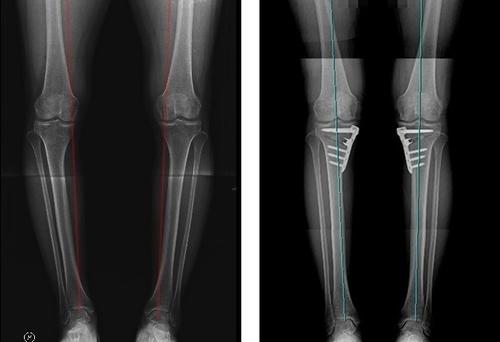

▲ O다리(내반 변형) 교정치료 전후 하지 정렬을 바로 잡으면 연골재생 치료의 효과가 높아진다

중년층에서 흔한 O다리 변형은 무릎 안쪽으로 하중이 집중되면서 내측 연골만 심하게 닳는 편마모를 만든다. 이를 해결하기 위한 치료가 휜다리 교정술인 ‘근위경골절골술(HTO)’이다. 근위경골절골술은 무릎 내측에 집중된 하중을 외측으로 분산시켜 연골이 더 이상 마모되지 않도록 무릎의 축을 바로 잡아주는 교정술이다. 본인의 관절을 보존하면서 통증을 줄이고 관절염 진행 속도를 늦출 수 있다는 점에서 활동량이 많은 50~60대 환자들에게 특히 적합하다.

하지만 절골술은 정렬을 교정하는 수술이지 연골을 재생시키는 수술이 아니다. 이미 내측에 연골 결손이 있는 중기 관절염 환자라면 연골 재생 치료를 함께 적용해야 최적의 결과를 얻을 수 있다. 이때, 가장 많이 병행되는 치료가 바로 카티스템 줄기세포 시술이다.

정구황 센터장은 “절골술이 관절의 마찰과 하중을 바로잡는다면, 카티스템은 손상된 연골 자체를 재생한다. 두 치료를 함께 적용하는 것이 중기 관절염 환자에게 가장 이상적인 조합”이라고 강조했다.